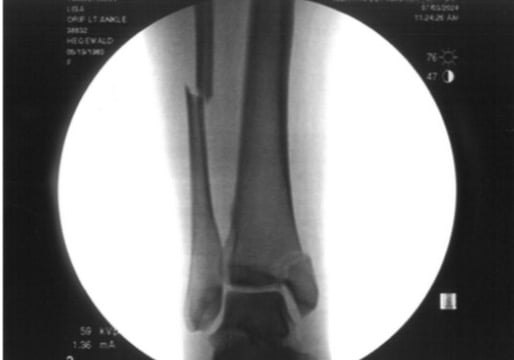

On June 27th, 2024, while biking eastbound on the Southeast Clinton Street neighborhood greenway, she crossed Cesar Chavez Blvd with a green light. As soon as she entered the intersection, a woman driving a blue Hyundai sedan southbound on Cesar Chavez slammed into her. The driver, then 21-year-old Sophie Bell, failed to stop at a red signal and didn’t even brake. A video (view it below) from a nearby resident shows Timmerman crumple to the ground on impact and begin wailing in pain. The collision caused multiple fractures to Timmerman’s ankle and several broken ribs.

Timmerman, 42, endured two surgeries to repair bones and spent months in pain and physical therapy sessions. She expects early onset arthritis and ankle replacement surgery are in her future. “I was a very serious cyclist prior to the accident, riding about 6,000 miles a year,” she shared with me via email. “And while I’m back to cycling now, I’m doing only a fraction of what I did before.”

For those that are curious, my current medical expenses were in excess of $140k. I was able to have that covered via a combination of different insurances, but the driver had only the minimum for Oregon, which is some of the lowest in the country. As the driver was a young person they have minimal assets, so that is an inherent systemic inequity that the outcome is fully dependent on who hits you. Any future expenses – which for me may include a full ankle joint replacement down the road – I will need to cover myself. I have been encouraging most people I know to revisit the coverage they have to protect against minimally insured or non insured drivers.